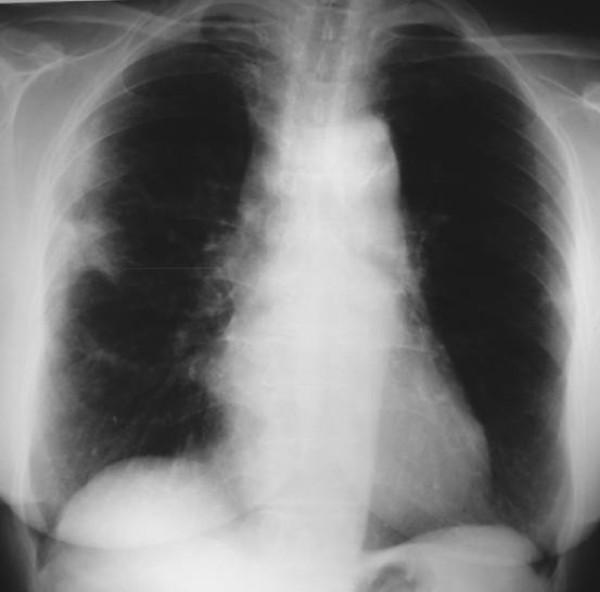

Here, we describe a rare case of acute fibrinous and organising pneumonia, in an otherwise healthy 65-year-old Greek woman who complained of dry cough, fever, weight loss and progressive dyspnoea. She had never been a smoker. Her clinical symptoms showed a rapid deterioration in the two weeks before admission, despite a course of oral antibiotics. After excluding infection and malignancy with routine laboratory tests and flexible bronchoscopy, high resolution computed tomography and video assisted thoracoscopic lung biopsy were performed. Diagnosis was based on radiological features typical of community organising pneumonia coupled with pathologic features characteristic of acute fibrinous and organising pneumonia. The patient was treated with corticosteroids and showed excellent clinical and radiological response three months after treatment initiation.

在此,我们描述一例罕见的急性纤维蛋白性和机化性肺炎病例,患者为一名65岁健康的希腊女性,主诉干咳、发热、体重减轻和进行性呼吸困难。她从不吸烟。尽管接受了口服抗生素治疗,但在入院前两周她的临床症状迅速恶化。通过常规实验室检查和可弯曲支气管镜检查排除感染和恶性肿瘤后,进行了高分辨率计算机断层扫描和电视辅助胸腔镜肺活检。诊断基于社区获得性机化性肺炎的典型放射学特征以及急性纤维蛋白性和机化性肺炎的特征性病理特征。患者接受了皮质类固醇治疗,治疗开始三个月后临床和放射学反应良好。